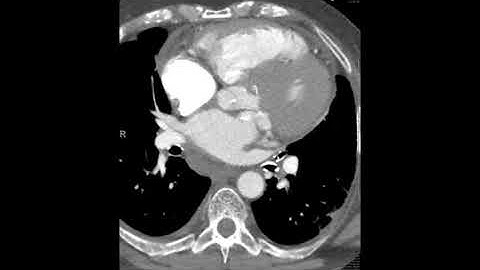

Mitral Annulus Calcification (MAC) & Caseous MAC